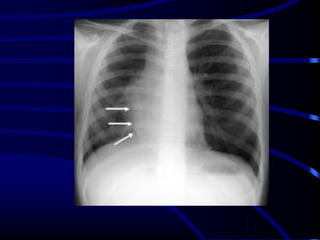

S Curve of

Golden

When there is a mass

adjacent to a fissure, the

fissure takes the shape

of an "S". The proximal

convexity is due to a

mass, and the distal

concavity is due to

atelectasis. Note the

shape of the transverse

fissure.

This example represents

a RUL mass with

atelectasis